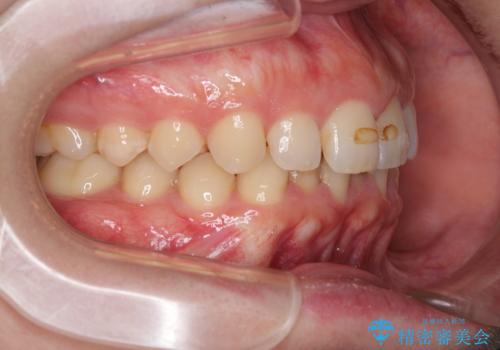

- 下の歯のがたつきを主訴に来院されました。

下の歯のがたつきと右の奥歯の噛みあわせ改善するために治療計画を立てることにしました。

右側臼歯部の咬合改善のために、臼歯部のみ部分的なワイヤー矯正を行い、咬合改善がみられてからインビザラインにて全体的な矯正を行なっていく治療計画を立てました。

噛み合わせをよくするために、ワイヤー矯正とインビザライン矯正のどちらの期間も必要な箇所にゴム掛けを行いながら治療を行いました。

下の前歯のがたつき改善にはIPR(歯と歯の間を削る処置)を行いました。

ゴム掛けを頑張っていただいたので、噛みあわせも改善され綺麗な歯並びになりました。